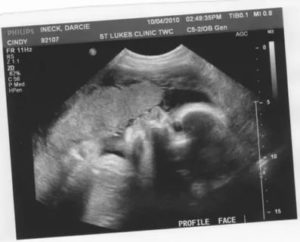

В это время врач, ведущий беременность, обязательно отправит вас на УЗИ, чтобы определить, действительно ли сейчас идет 31-32 неделя беременности. Вес плода определяется также по результатам данного обследования.

УЗИ

Это метод диагностики, который дает возможность врачу оценить состояние ребенка, а маме впервые увидеть своего кроху. В последнее время технологии сделали огромный скачок, теперь поход на УЗИ напоминает посещение зрительного зала. Обычно будущая мама приходит вместе с папой, а порой и бабушкой ребенка, и все могут понаблюдать за движениями крохи в животе.

Мы хотели бы более детально рассмотреть, что такое процедура УЗИ 31-32 недели беременности. УЗИ на этом сроке призвано определить, являются ли размеры плода соответствующими развитию. Второй момент – узнать, перевернулся ли ребенок головкой вниз.

Обычно обратно он перевернуться уже не сможет, так как продолжает прибавлять в весе. Параллельно врач оценит индекс амниотической жидкости. Он должен быть в районе 80-250 мм. Если меньше, то ставят диагноз маловодие, а если больше, то многоводие.

Узи на 32 неделе беременности

На 32 неделе женщины чаще всего проходят третье плановое УЗИ. Врач оценивает функцию плаценты: положение плода в животе на 32 неделе беременности, к какой стенке прикреплена и на каком расстоянии по отношению к шейке матки, толщина плаценты и ее структура.

Эти показатели могут очень многое рассказать о возможной инфекции, воспалении, осложнении во время родов. Основная задача УЗИ на этом сроке исключить пороки развития и оценить состояние плаценты – степень ее зрелости, кровоток в ней.

Кроме того, с помощью Узи на 32 неделе беременности врач уточняет физическое состояние малыша, оценивается его положение (головное, тазовое, иное),производится биометрия (измеряются размеры головки, окружность или средний диаметр животика, длина бедренной кости).

Как правило, на 32 неделе женщина проходит третье плановое УЗИ. При осмотре оценивается самочувствие ребенка, его предлежание и не обвивает ли пуповина шею младенца. На этом сроке устанавливается, в каком состоянии находится шейка матки, насколько ребенок вырос, определяется степень зрелости плаценты.

Как правило, на 32 неделе беременности УЗИ проводят планово, то есть, на это время назначают третий ультразвуковой скрининг. Что смотрят, проводя УЗИ на 32 неделе беременности? Прежде всего, проводится УЗИ плода на 32 неделе беременности, то есть, специалист проводит измерение основных показателей:

УЗИ в 32 недели позволяет не только убедиться в том, что с плодом все нормально. Исследование позволяет определить следующие параметры:

Нормальный объем околоплодных вод на этом сроке – около 1200 мл.

- определить степень зрелости плаценты, норма для этого срока – первая степень зрелости;

- проверить в каком состоянии шейка матки, укороченная шейка – это признак угрожающих преждевременных родов.